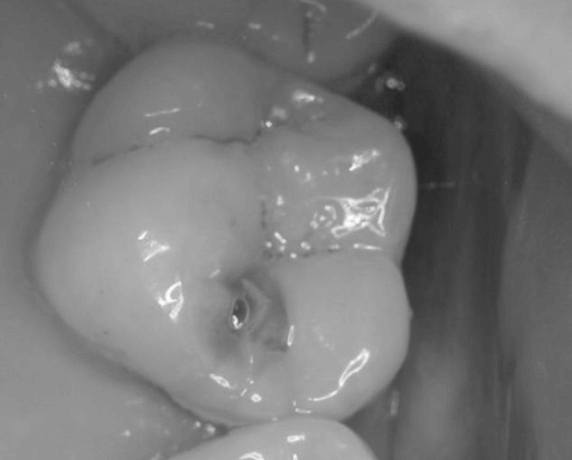

Kaz hluboký

Zasahuje do zuboviny a jedná se o nevratný děj (neremineralizuje). Je nutné jej ošetřit zubní výplní. Kaz blízký zubní dřeni (nervu) vyžaduje překrytí bioaktivním preparátem na bázi Ca(OH)2 a ošetření zubní výplní nebo dostavbou. Je zde vysoké riziko zánětu zubní dřeně (nervu).